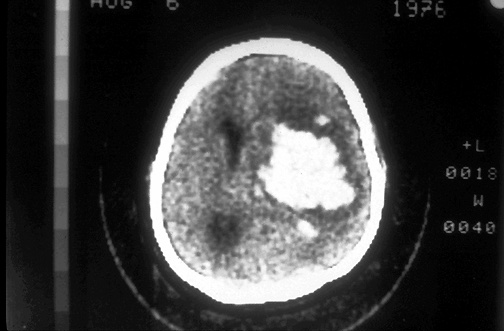

Click on the intracerebral hemorrhage in the CT scan below:

This computed tomographic (CT) scan of the head in transverse view demonstrates an area of hemorrhage in a patient with a history of hypertension.